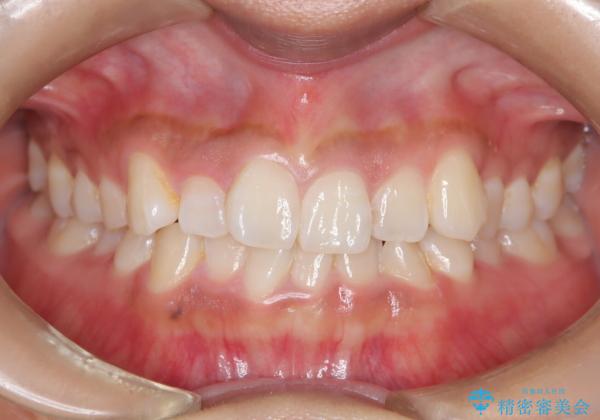

- 前歯の叢生(がたつき)を主訴に来院された患者様です。以前マウスピース矯正をされていたそうでしたが、自身での継続が難しいことなどを理由に、ワイヤー矯正にて改めて矯正治療を希望されました。非抜歯にて治療を計画し治療を行いました。

歯の動きが良く、スムーズに治療を終了しました。一般的にワイヤー矯正はブラッシングが難しいのですが、毎回一生懸命セルフケアをされていたのが印象的です。治療においては、歯の衛生状態も一緒にチェック致します。